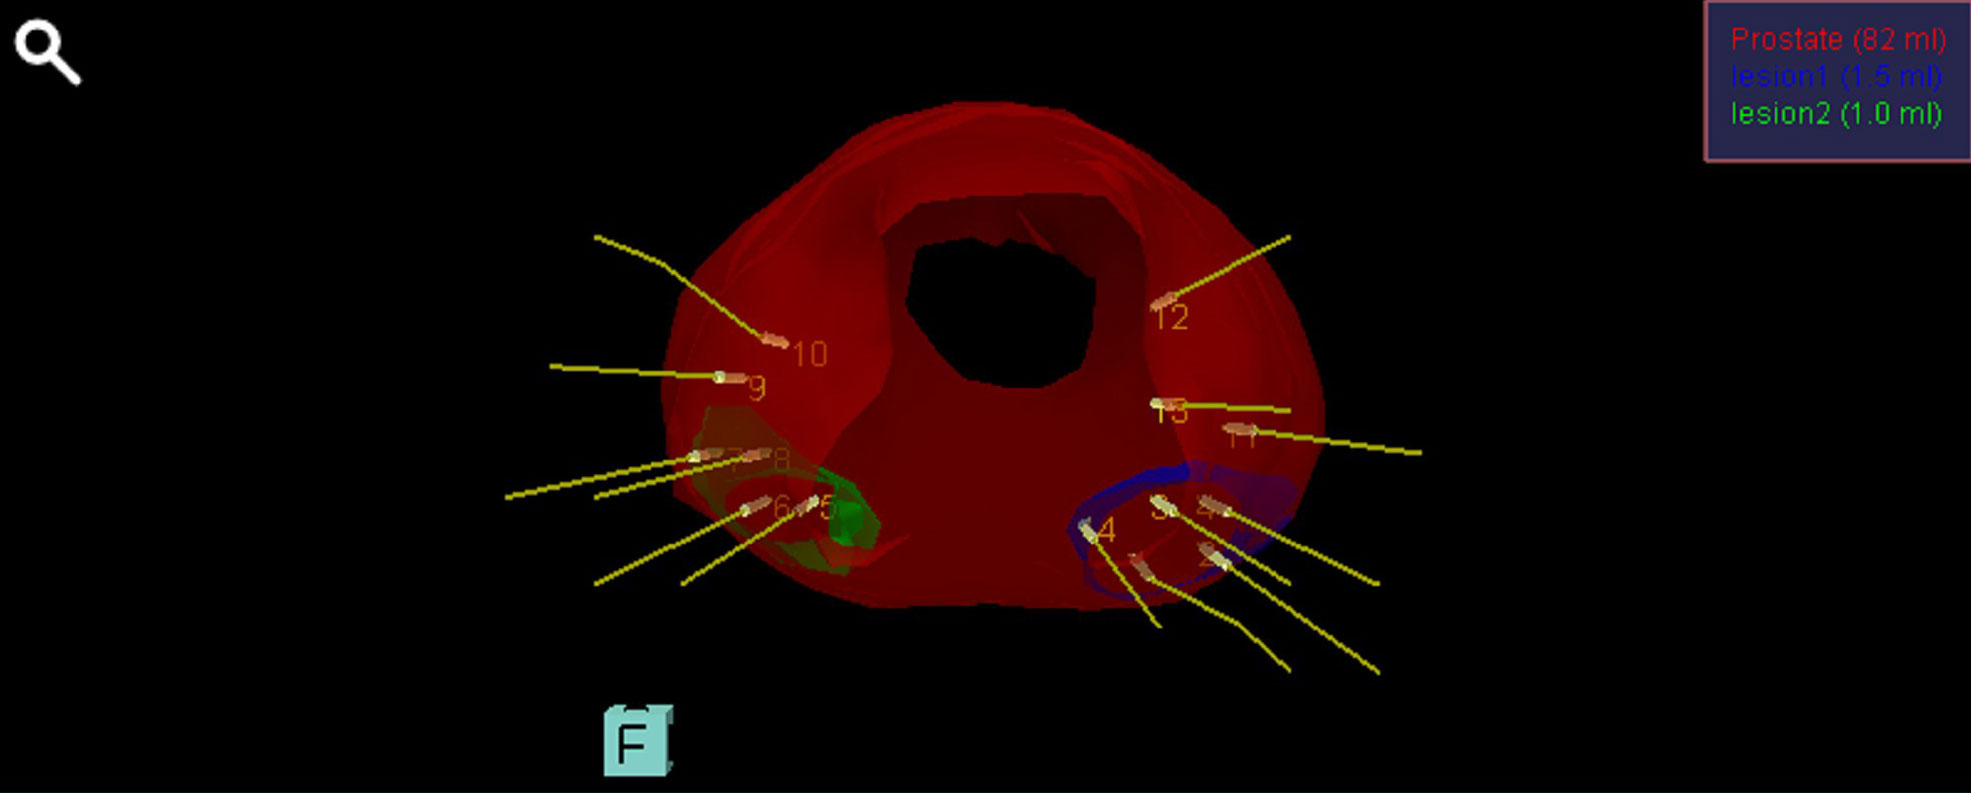

Αναφορά του συστήματος Biopsee όπου φαίνονται οι στοχευμένες βιοψίες στις βλάβες (δε) & (αρ) που μας εδειξη η Πολυπαραμετρικη MRI προστάτη , όπως και κάποιες στοχευμένες άμφω.